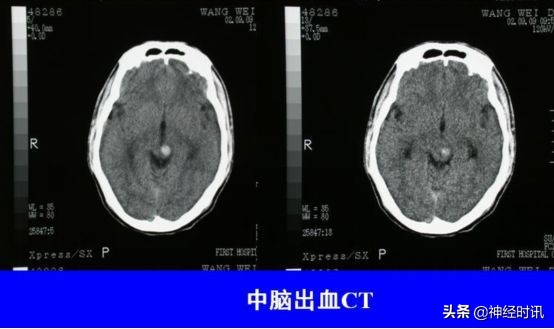

中脑出血

出血量少→同侧或双侧动眼神经损害,眼位异常,伴对侧或双侧锥体束征。

大量出血→深昏迷、双侧瞳孔散大,立即死亡。